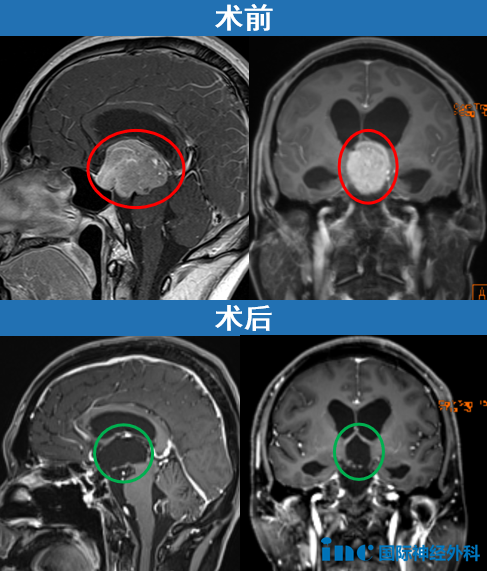

2025年6月,35岁江先生发现鞍区及鞍上巨大垂体瘤引发阻塞性脑积水。巨大肿瘤压迫脑干、第三脑室及导水管。"手术风险极大,难度过高,建议前往其他医院就诊……"

不放弃之下迎来转机。无需开颅,INC福教授在北京天坛医院通过经鼻内镜手术成功切除巨大垂体瘤。

2个月后,患者逐渐恢复正常生活。"目前状况良好,一切正常,非常感谢福教授!"随访视频显示,江先生一家生活幸福,面容洋溢幸福笑容。